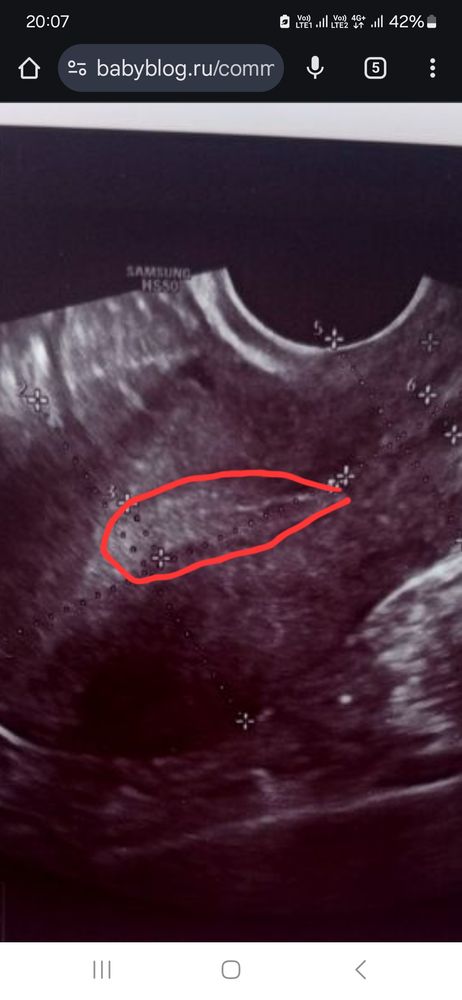

Светлана , вот смотрите первая и вторая фаза, мне кажется у вас не было овуляции и эндометрий на 1 фазу, т.к. видно линию смыкания, но я не узист конечно, просто уже за кучу узи у себя различаю Изображение Изображение

Аня, вот это как я понимаю эндометрий или нет? Изображение

Светлана , вот у вас эндометрий, слева это ближе ко дну матки, а справа к шейке Изображение